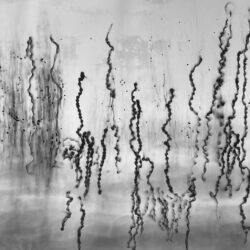

Montaña o prótesis Montaña

Comencé este proyecto hace tres años, cuando se me detectó cáncer de mama. El autorretrato me ayudó a mirar los cambios que me aquejaban. Hoy, al ver esas imágenes, descubro las distintas prótesis que se nos proponen. En Montaña o Prótesis montaña, incluyo a una comunidad a través de sus objetos personales. No es mi historia, ni la del cáncer, sino una narración colectiva, la de la naturaleza en su tiempo contemporáneo y nosotras en ella. Vemos pechos de semillas, mamas de silicon, cabellos dorados, todos descansando sobre la cama, la mesa, mientras nosotras, miramos las montañas. La prótesis es la imposición de la normalidad, pero también es su fracaso. El cuerpo biológico se recompone a través de la prótesis. ¿Pero cómo verla? ¿Como fisura, como ausencia, como cicatriz? Aquí propongo verla en relación con la montaña, como naturaleza sometida que debe ser cuidada.

Laksmi de Mora (1981)

Laksmi de Mora es licenciada en Antropología Social; maestra en Imagen, Arte, Cultura y Sociedad; y Doctora en Humanidades por la Universidad Autónoma del Estado de Morelos. Se formó como fotógrafa profesional en la School of Photography and Visual Media en la Ciudad de México. En el 2023 obtuvo el apoyo, por parte de la Secretaría de Cultura para realizar una Residencia Artística en Buenos Aires, Argentina. Participó en el Seminario de Producción Fotográfica del Centro de la Imagen (2024). Actualmente es profesora de fotografía y teoría de la imagen en el Centro Interdisciplinario de Investigación en Humanidades, UAEMor. Sus líneas de investigación son la imagen, el género y la fotografía. Su trabajo fotográfico gira en torno al cáncer de mama.